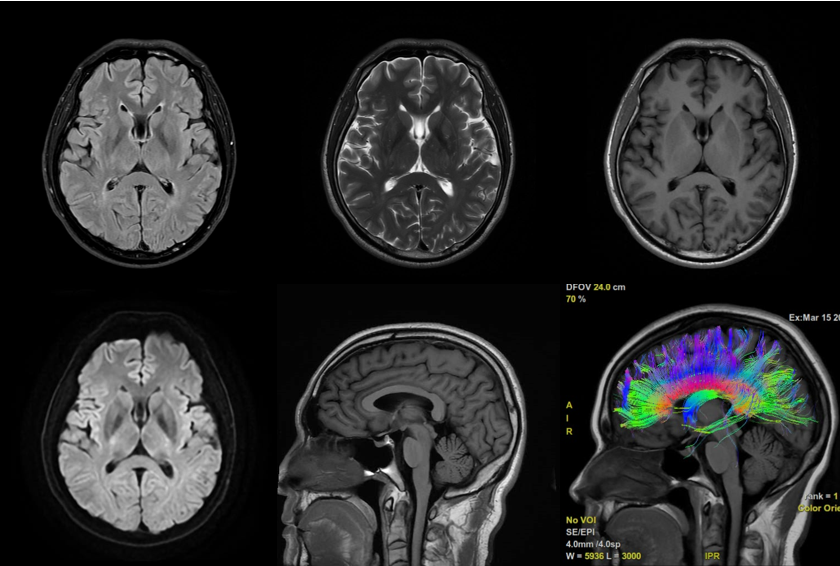

颅脑:脑肿瘤、脑血管病变、癫痫、痴呆、垂体病变等;

颅脑平扫+DTI

3.0T高场强带来的极致成像效果,能清晰显示神经系统、体部脏器、骨关节、心血管等部位的细微病变,无论是早期脑梗塞、微小脑肿瘤,还是肝癌、胰腺癌等恶性肿瘤的早期筛查,亦或是肩袖撕裂、半月板损伤等软组织损伤,都能精准捕捉,让病灶无处隐藏。

依托3.0T强磁场,设备可实现多种高端功能成像:发病30分钟即可发现病灶的DWI弥散加权成像、无需造影剂的MRA磁共振血管成像、无创显示胆道系统的MRCP胰胆管成像、辅助鉴别肿瘤良恶性的波谱分析(MRS),从单纯的结构成像升级为功能成像,诊断维度更全面。